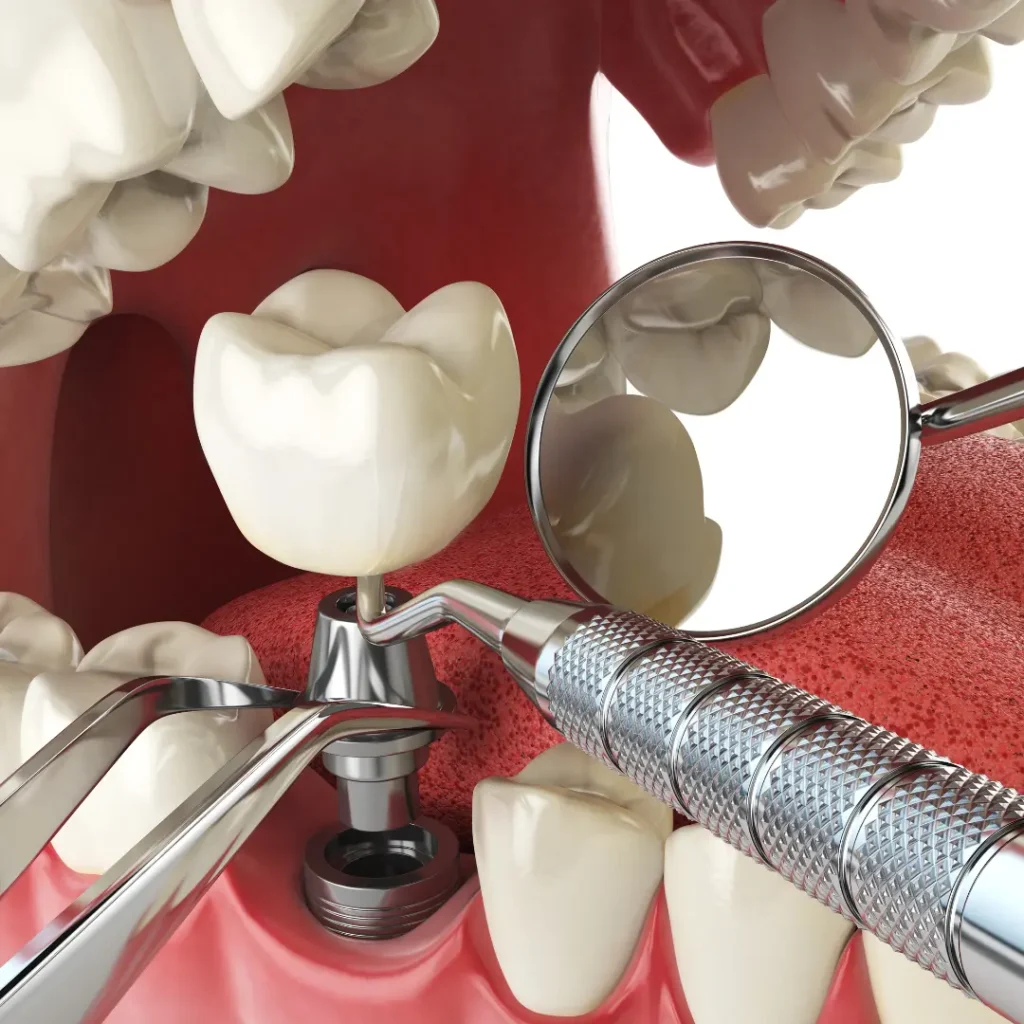

We provide several types of dental implants, including single-tooth implants, implant supported bridges, and full-arch restorations. For emergencies, we assess what’s best depending on your situation and oral health.

Can a damaged implant be repaired or replaced?

Yes. Depending on the issue, we may repair the implant restoration, replace the artificial tooth root, or adjust the surrounding crown or abutment. Our emergency dental services ensure quick, effective care to restore your implant.

Yes, in some emergency cases, we can place an implant immediately after extraction, provided the bone and soft tissue conditions are favorable. This is called immediate placement and reduces the number of visits.